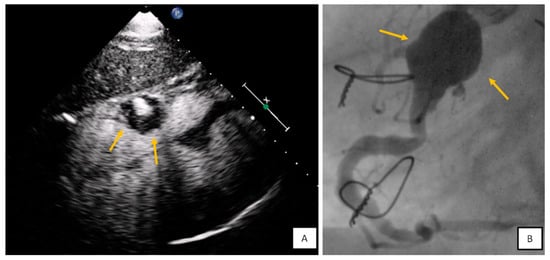

3.2. Transesophageal Echocardiography

- Ragland, M.M.; Tak, T. The role of echocardiography in diagnosing space-occupying lesions of the heart. Clin. Med. Res. 2006, 4, 22–32. [Google Scholar] [CrossRef]

- Wang, X.; Li, Y.; Ren, W.; Yu, X.; Tan, X. Clinical diagnostic value of contrast-enhanced ultrasonography in the diagnosis of cardiac masses: A pilot study. Echocardiography 2020, 37, 231–238. [Google Scholar] [CrossRef]